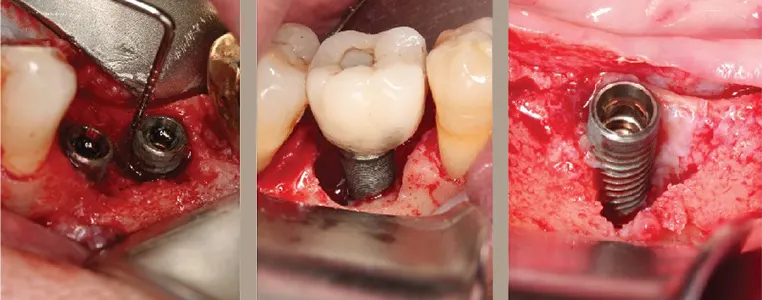

در افرادی که با حساسیت به ایمپلنت دندان مواجه هستند، می بایست ایمپلنت خارج گردد، در واقع امکان استفاده از تیتانیوم در این گروه از افراد وجود ندارد، اما این به معنای عدم وجود راهکارهای جایگزین نمی باشد.

با وجود پیشرفت های گسترده در دنیای پزشکی، امروزه امکان استفاده از ایمپلنت های غیر فلزی که تحت عنوان ایمپلنت های سرامیکی شناخته می شوند در افراد مبتلا به حساسیت به ایمپلنت دندان وجود دارد، در ساخت این نوع از ایمپلنت ها از اکسید زیرکونیوم استفاده می شود.

ایمپلنت های ساخته شده از زیرکونیا دارای فواید و مزایای بسیاری می باشند که از این جمله می توان به دوام و استحکام بالای آن اشاره کرد که یکی از پارامترهای مهم برای مواد مصرفی در این زمینه می باشد، و سبب افزایش ماندگاری آن می گردد.

از طرفی زیرکونیا زیست سازگار بوده و سبب تحریک واکنش های آلرژیک نمی گردد، از این رو گزینه ای ایده آل برای افراد حساس و با سطح واکنش آلرژیک بالا می باشد، از دیگر مزایای این ترکیب می توان به هم رنگ بودن آن با دندان اشاره کرد، علاوه بر آن از نظر بهداشتی نیز به دلیل عدم تجمع جرم بر سطح آن بسیار مناسب می باشد.